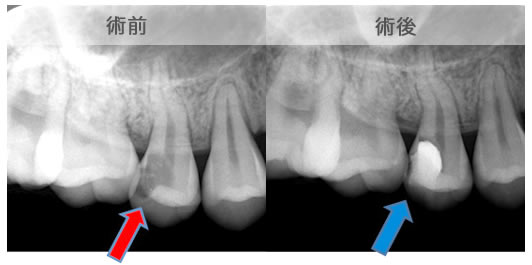

頬側骨壁の根尖部まで無くなっています。

MTA根充後11ヶ月で透過像が消失し、根尖部が正常化しました。

頬側骨の喪失が見られましたが17ヶ月で回復しました。

頬側骨の回復が確認できます。

| 治療説明 | 左下第一小臼歯の頬側根尖部からの排膿、痛みはないそうです。X線画像では根尖部に透過像を認められます。 頬側の骨も失われており、歯髄が死んだことが原因と考えられます。修復物を除去後根管治療を行い、根管充填後、透過像は消失、頬側骨も再生されていました。 |

|---|---|

| 治療期間 | 6〜24ヶ月 |

| 治療費用 | 150,000〜300,000円 |

| 治療に伴うリスク | 根管内からの治療で根尖病巣が治らない場合は、外科的に根尖病巣を除去する必要があります。 再根管治療を繰り返す場合、歯根の厚みが薄くなり、歯根破折のリスクが高まります。 |

原因は赤の矢印が指す、根の周りの病巣でした。

治療後は青い矢印が指す場所には、黒い病巣が消失しています。

| 治療説明 | 自覚症状で歯が浮いた感じがしていました。上顎大臼歯・頬側根の根尖部にX線透過像の病巣があります。根充剤を除去・拡大清掃・根管充填を行いました。根尖から根充剤がはみ出ていますが、根尖部のX線透過像は見られなくなりました。そこ後、自覚症状もなくなりました。 |

|---|---|

| 治療期間 | 6〜24ヶ月 |

| 治療費用 | 150,000〜300,000円 |

| 治療に伴うリスク | 根管内からの治療で根尖病巣が治らない場合は、外科的に根尖病巣を除去する必要があります。 再根管治療を繰り返す場合、歯根の厚みが薄くなり、歯根破折のリスクが高まります。 |